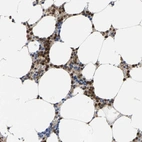

Immunohistochemical staining of human bone marrow shows strong positivity in a subset of hematopoietic cells.